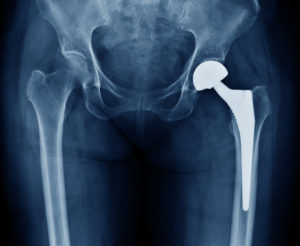

Types of Orthopedic Implants

If you've ever suffered a traumatic injury from an accident, or degeneration of a joint or bone over time from a chronic medical condition, an orthopedic implant might be needed to stabilize your muscular system, and improve your mobility and flexibility. An orthopedic implant is a manufactured [Read More]